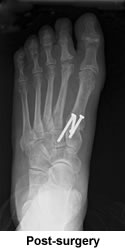

After two previous surgeries for a bunion and a hammer toe, both of which left my feet in even worse shape, I was leery of risking any more. However, as my feet continued to fall apart and the pain worsened, I knew that something further must be done. I had heard good things about New England Baptist, but still somewhat dubious, I took the plunge and called the hospital for a referral to their best orthopedic foot surgeon. Without hesitation they recommended Dr. Leavitt. Not until after checking his web site did I make the appointment for a consultation. He was very thorough in his explanation of what he might do to correct my problems and answered my many questions about the surgery, the time I would spend in recovery, and how I might manage the eight weeks of being non-weight bearing.

Prior to actually committing myself to the surgery, I contacted Beverly Millar, whose written testimonial was among several on his web site. Thanks to Beverly's helpful advice and reassurance, I finally arrived at one of the most difficult, as well as one of the best, decisions of my life and set the date for surgery. Beverly put me in touch with another of Dr. Leavitt's patients, whose operation was three weeks ahead of mine. Both women, Beverly and Kathy, were familiar with the Roll-A-Bout, an incredible little walker recommended by Dr. Leavitt, without which, convalescence would have been far more difficult. Kathy became my step-by-step guide throughout the process with frequent updates on her progress, preparing me for what to expect next. Nothing was as difficult as I had imagined it would be. With the Roll-A-Bout I was able to zip around the house and eventually up and down the aisles of the supermarket. The ten weeks of disability--which I had dreaded--turned out to be surprisingly comfortable and stress free. The end results were spectacular.

Three months after the second surgery I had the first pedicure of my life, bought my first pair of flip-flops, and headed for Florida. What a thrill to walk on a beach barefoot and pain free! What a joy to lounge by a pool without hiding my feet under a towel! I'm thrilled with my new feet, fused bones, new joints and all. I can now enjoy pilates, long walks, dressy evening affairs, and traversing airport terminals without agony. For once in my life I'm neither ashamed nor embarrassed by my feet. And best of all, I can get through a day without moaning, "My feet are killing me!"